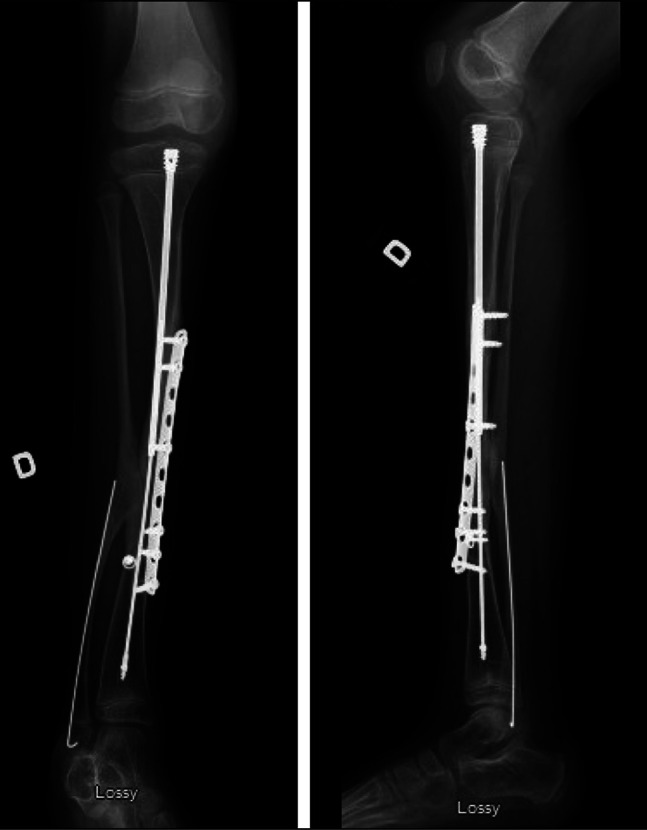

1型神经纤维瘤病(NF-1)导致皮肤、神经和肌肉骨骼表现。先天性胫骨假关节治疗被认为是实现骨愈合的积极手段。大多数患者在治疗结束时由于病理性骨切除和不对齐而导致肢体短。患者可能出现的表现之一是肢体局部半肥厚。在我们的病例中,我们首次报道了同一条腿先天性胫骨假关节和半肥厚并存的情况。

Neurofibromatosis type 1 (NF-1) leads to cutaneous, neurological, and musculoskeletal manifestations. Congenital pseudarthrosis of the tibia treatment is considered aggressive in achieving bone union. Most of those patients get a short limb at the end of treatment because of pathological bone resection and malalignment. One of the manifestations that can appear in patients is localized hemihypertrophy of the limb. In our case, we present the first time a coexistence of congenital pseudarthrosis of the tibia and hemihypertrophy in the same leg was reported.